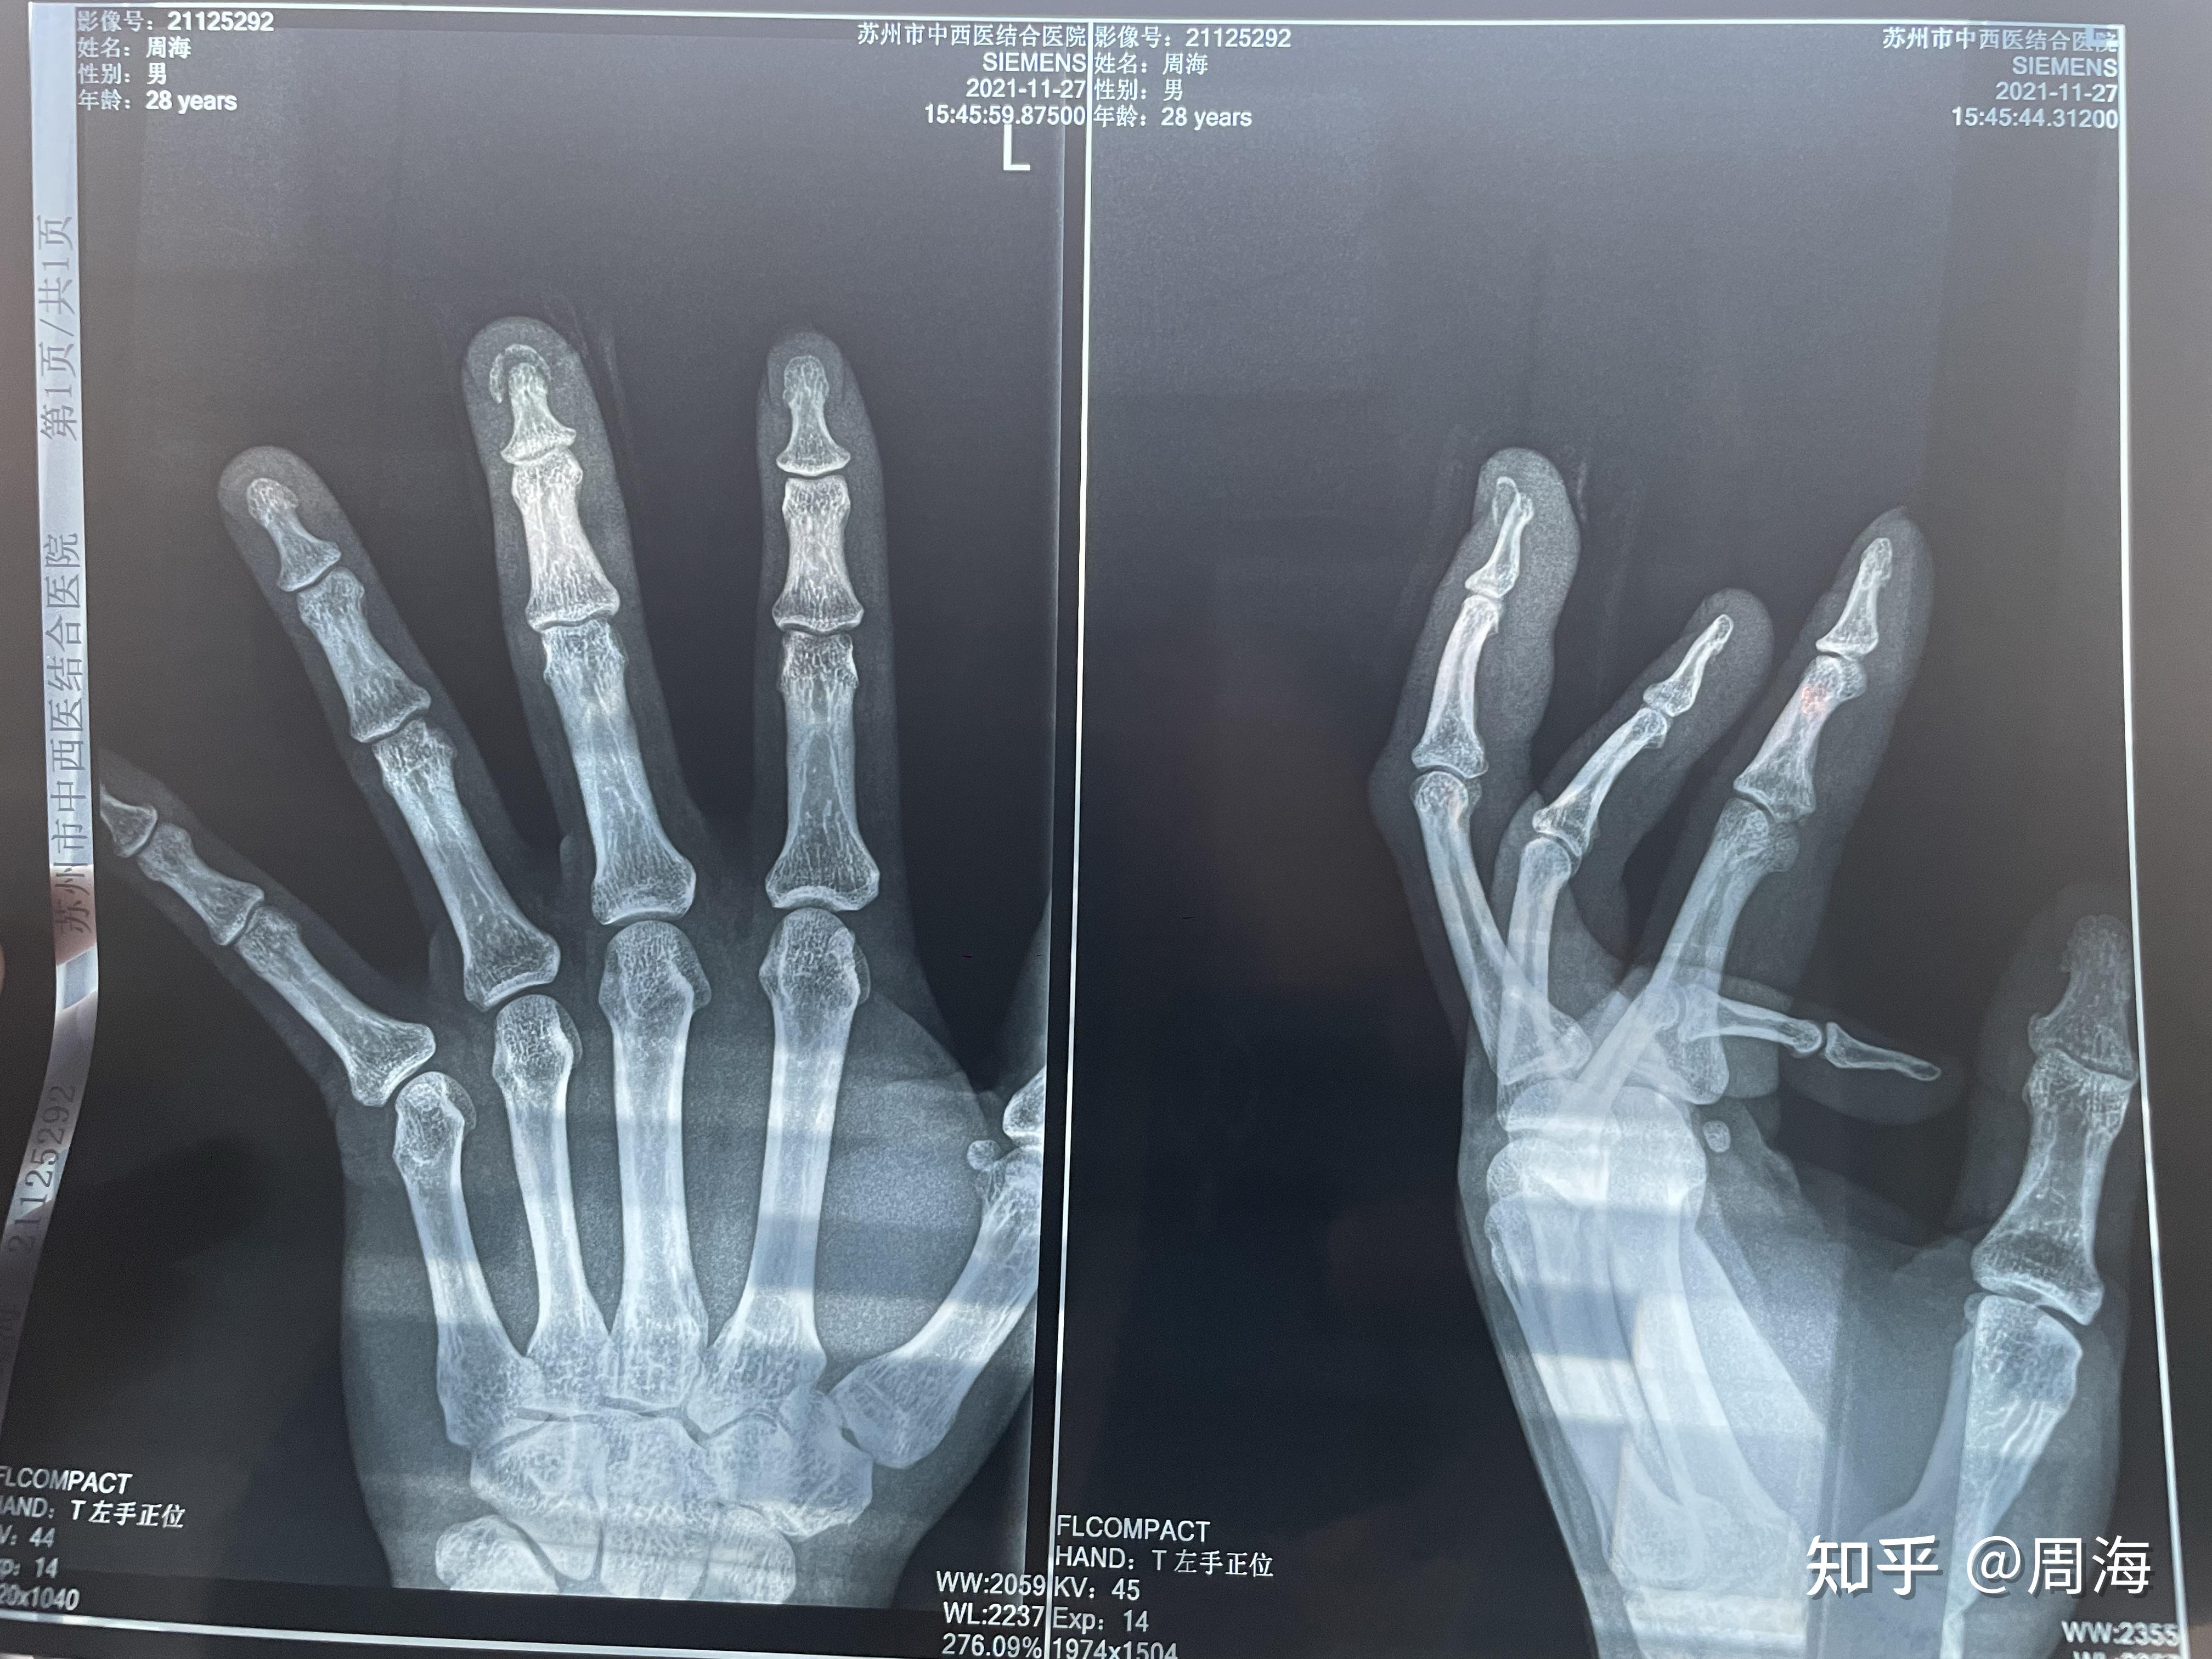

病例分享28岁男患被铡草机铡伤导致中指完全离断行断指再植成活